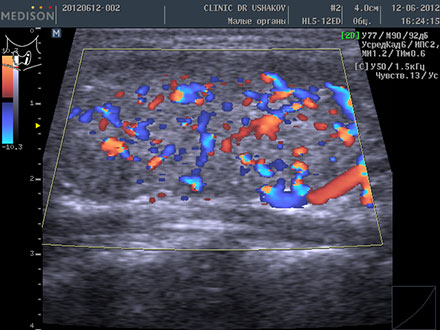

| В левой доле (в сосудистом режиме; ЦДК) заметно усиление кровотока ― свойственно избыточному напряжению железы | В левой доле (в сосудистом режиме; ЦДК) кровоток восстановился до оптимальной интенсивности ― нормальное состояние железы |